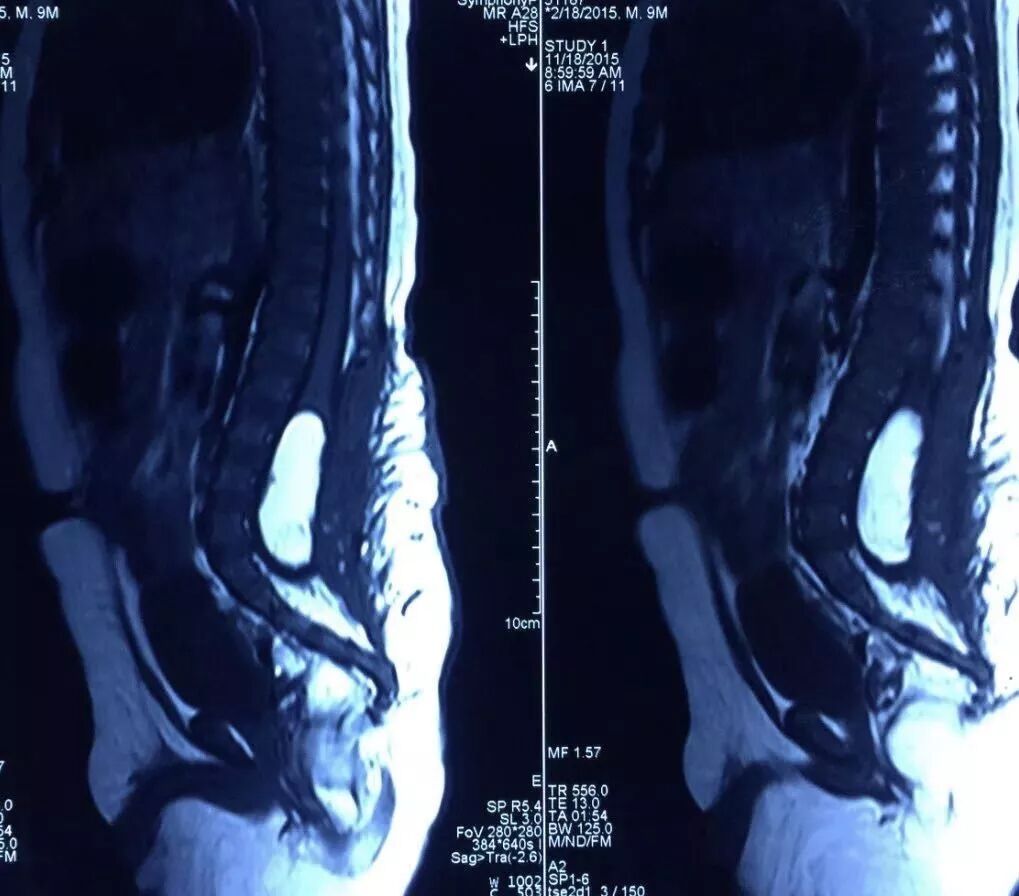

术前影像检查

MR扫描显示骶尾段脊髓脊膜膨出,脑积水,Chiari畸形II型。

术前诊断:骶尾段脊柱裂(脊髓脊膜膨出),Chiari畸形II型,脑积水,双侧神经源性马蹄内翻足。